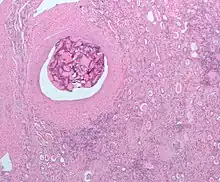

L'embolisation est un procédé thérapeutique consistant en l'occlusion sélective de vaisseaux sanguins par l'injection d'un agent embolique. Elle est utilisée dans le traitement d'une large variété de pathologies et est généralement réalisée par un radiologue interventionnel.

Les tumeurs hépatiques peuvent aussi bénéficier de cette modalité thérapeutique et il est même possible de réaliser dans ce cas une chimio-embolisation intra-artérielle. L'occlusion des artères nourricières par l'agent embolique est alors associée à l'injection intra-tumorale d'une chimiothérapie.